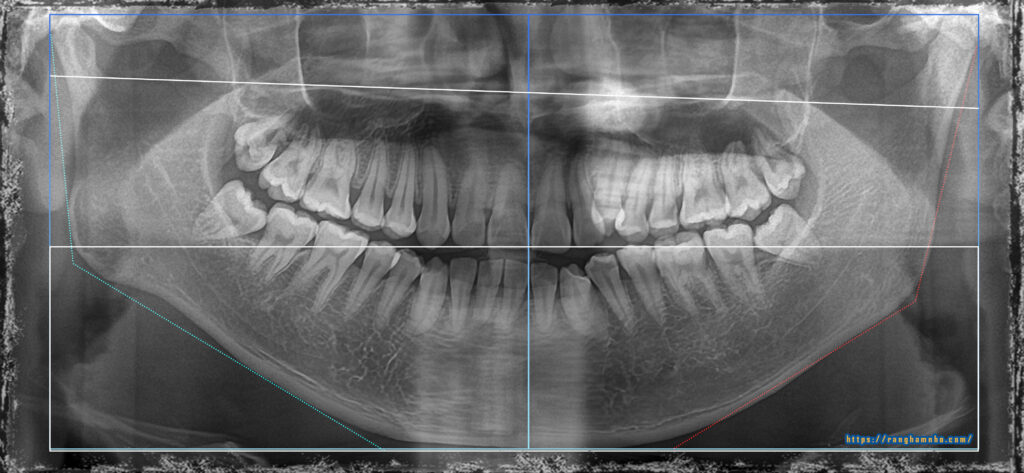

BN nam sinh năm 1994 khớp cắn hạng III, răng chen chúc. BN có sự phát triển không đồng đều của xương hàm dưới hai bên dẫn đến biến chứng lệch mặt. Kết hợp cả yếu tố sai khớp cắn do răng làm hàm dưới vừa lệch do xương lại vừa lệch do thích nghi chức năng. BN đã được nhổ 3R4 để giải quyết vấn đề chen chúc răng và kéo lùi nhóm răng cửa dưới.

Tình hình khi gặp gỡ: còn nhiều khoảng nhổ răng, khớp cắn ngược răng cửa, cắn chéo nhóm răng hàm cung 1. Đường giữa hàm dưới lệch nguyên 1 răng cửa. Mặt thẳng lệch rất rõ, cằm đưa hẳn sang bên phải.

Kết quả: đường giữa gần như thẳng, xương hàm dưới định vị về vị trí bình thường. Khuôn mặt cải thiện khá so với trước điều trị nhưng không thể hoàn hảo do căn nguyên sai lệch kết hợp đến từ sai lệch xương ![]()